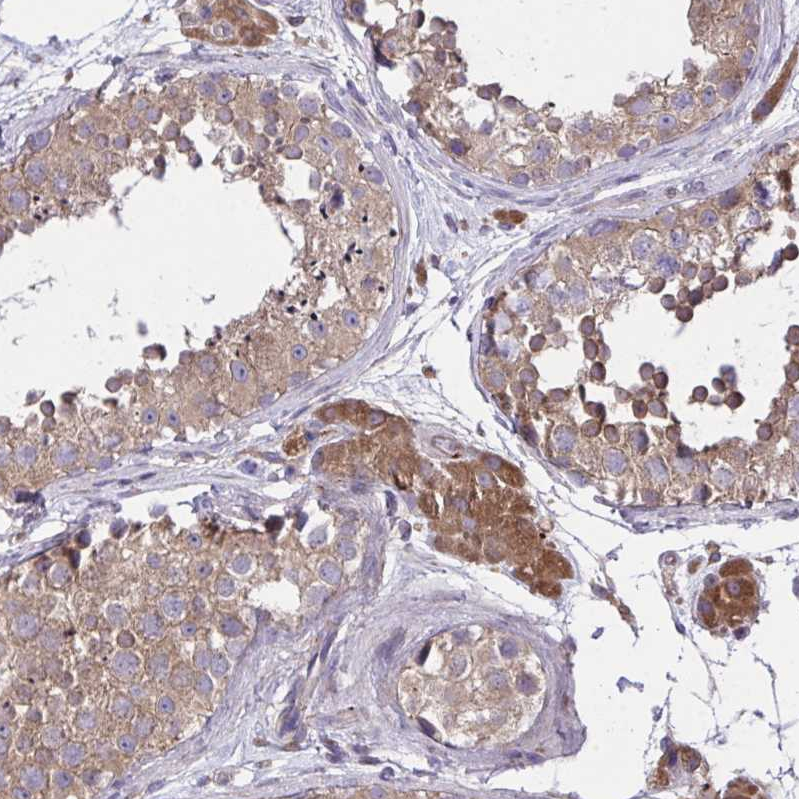

Immunohistochemical staining of human kidney shows strong cytoplasmic positivity in cells in tubules.